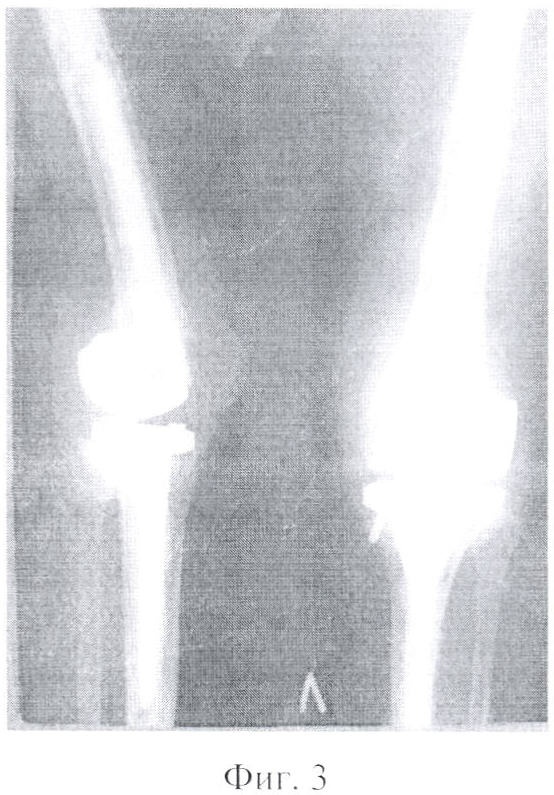

Фигура 3 – послеоперационные снимки. Имплантирован связанный шарнирный эндопротез коленного сустава «Феникс» (2003 г.).

По поводу ревматоидного поражения левого коленного сустава в 2003 году выполнено тотальное эндопротезирование левого коленного сустава эндопротезом «Феникс» (фиг.1, 2, 3).